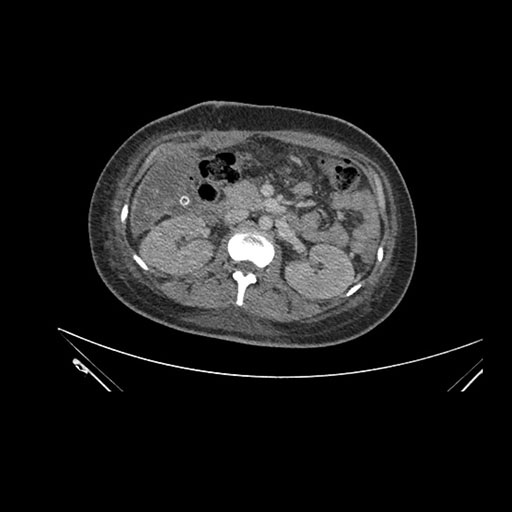

Axial Venous

Imaging analysis

Based on initial findings, which issue(s) would you be most concerned about?